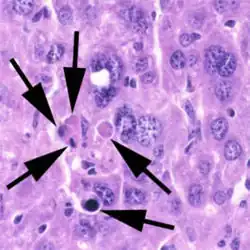

In pathology, a Councilman body, also known as a Councilman hyaline body or apoptotic body, is an eosinophilic globule of apoptotic hepatocyte cell fragments. Ultimately, the fragments are taken up by macrophages or adjacent parenchymal cells.[1] They are found in the liver of individuals suffering from acute viral hepatitis, yellow fever, and other viral syndromes.[2]

When referring to Councilman bodies, it is crucial to understand the term "apoptotic body". Apoptotic bodies are a peculiar type of extracellular vesicle that are left over pieces from cells that have undergone apoptosis, programming cell death.[3] The dying cells release varying amounts of closed, subcellular pieces that are often large for extracellular vesicles that may include forms of protein, DNA and RNA fragments, chromatin, lipids, cytosol, and organelles.

Hepatocytes are the liver's primary parenchymal cells, forming 80% of the liver's mass and 60% of its cells. They are round in shape and contain a nucleus and organelles that contribute to metabolic and secretory functions.[5] Hepatocytes also play a pivotal role in liver inflammation.[6] Councilman bodies are often named for the hepatocytes undergoing apoptosis, which occurs in the portal tracts and lobules of the liver. Inflammation of the liver is caused by the cytotoxic killing of hepatocytes, or Councilman bodies. Eventually, this inflammation leads to liver damage in viral hepatitis.[7] Through the use of double immune fluorescence methods, HBsAg and/or HBcAg (hepatitis B core antigen) are present in Councilman bodies in the liver.[8]

With a bright field microscope, Councilman described typical, discrete, necrotic lesions in human hepatic cells of those infected with yellow fever.[9] He noted that the bodies appeared to be red in hematoxylin and eosin-stained sections of hepatic tissue, while being circumscribed, varying in size, round or irregular shape, and having numerous vacuoles of different sizes.